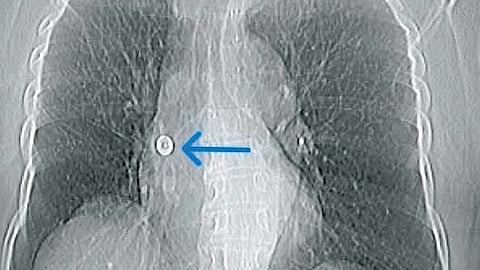

55 ವರ್ಷದ ಮಹಿಳೆ ಅಂಗಡಿಯಲ್ಲಿ ಬಟ್ಟೆ ಶಾಪಿಂಗ್ ಮಾಡವಾಗ ಮಹಿಳೆ ಪಿನ್ ಅನ್ನು ತನ್ನ ಬಾಯಿಯಲ್ಲಿ ಇರಿಸಿಕೊಂಡಿದ್ದು, ಈ ವೇಲೆ ಸೀನುವಾರ ಪಿನ್, ಬಲ ಶ್ವಾಸಕೋಶದ ಬ್ರಾಂಕಸ್ ಇಂಟರ್ಮೀಡಿಯಸ್ ಎಂಬ ಭಾಗದಲ್ಲಿ ಸಿಲುಕಿಕೊಂಡಿದೆ.

ಬಳಿಕ ಆಸ್ಟರ್ ಸಿಎಂಐ ವೈದ್ಯರು ಚೆಸ್ಟ್ ಎಕ್ಸ್-ರೇ ಮತ್ತು ಸಿಟಿ ಸ್ಕ್ಯಾನ್ ಸೇರಿದಂತೆ ವಿವರವಾದ ಸ್ಕ್ಯಾನ್ಗಳನ್ನು ಮಾಡಿಸಿದ್ದಾರೆ. ಈ ವೇಳೆ ಶ್ವಾಸಕೋಶದಲ್ಲಿ ಪಿನ್ ಸಿಲುಕಿಕೊಂಡಿರುವುದು ಕಂಡು ಬಂದಿದೆ.